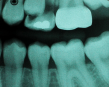

Molar migrations after loss of first molars, 8-year history: 1999

Figure 28

Molar migrations after loss of first molars, 8-year history: 2003

Figure 29

Molar migrations after loss of first molars, 8-year history: 2007

Figure 30

In 1998, a 7-year-old boy was brought in for emergency care with the chief complaint of toothache of the mandibular left permanent first molar. The malformed tooth was non-restorable and extracted, with no other treatment options. The child was not returned for continuing routine care but was returned on an emergency basis in 1999. He had a dentoalveolar abscess of the severely carious maxillary left permanent first molar, and the tooth was judged non-restorable (Figure 28). That molar was extracted. The patient was not returned to the office again until 4 years later, in 2003. The maxillary second molar had migrated into good position distal to the second premolar, and the third molar followed into place (Figure 29). The mandibular second molar was tipped mesially, followed by the crown of the third molar. Four years after that (2007), the patient returned as a 15-year-old. The second and third molars had migrated into position, with no orthodontic intervention (Figure 30).